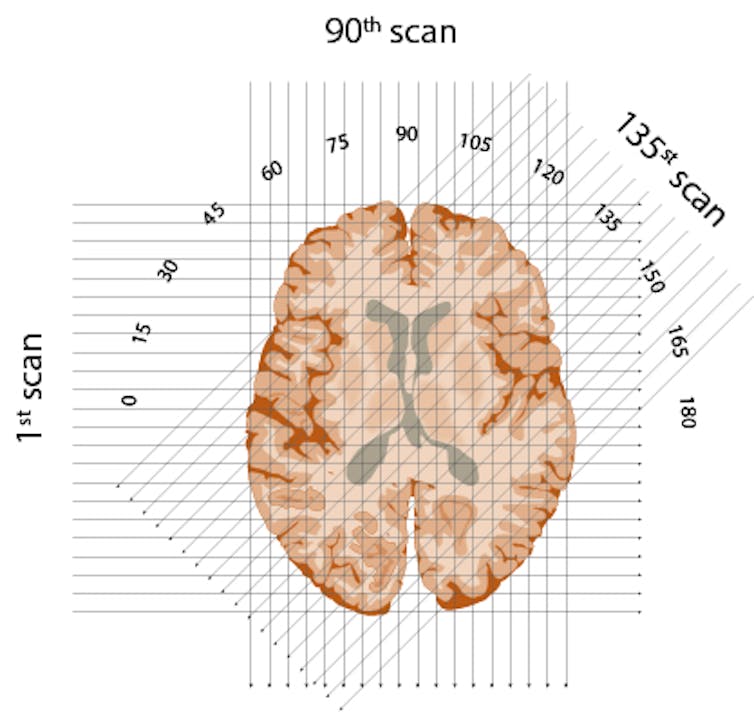

First, he would conceptually divide the brain into consecutive slices – like a loaf of bread. Then he planned to beam a series of X-rays through each layer, repeating this for each degree of a half-circle. The strength of each beam would be captured on the opposite side of the brain – with stronger beams indicating they’d traveled through less dense material.

Calculating the strength of each X-ray once it’s passed through the object, and working backward with an impressive algorithm, it is possible to construct an image.Edmund S. Higgins, CC BY-ND

Finally, in possibly his most ingenious invention, Hounsfield created an algorithm to reconstruct an image of the brain based on all these layers. By working backward and using one of the era’s fastest new computers, he could calculate the value for each little box of each brain layer. Eureka!